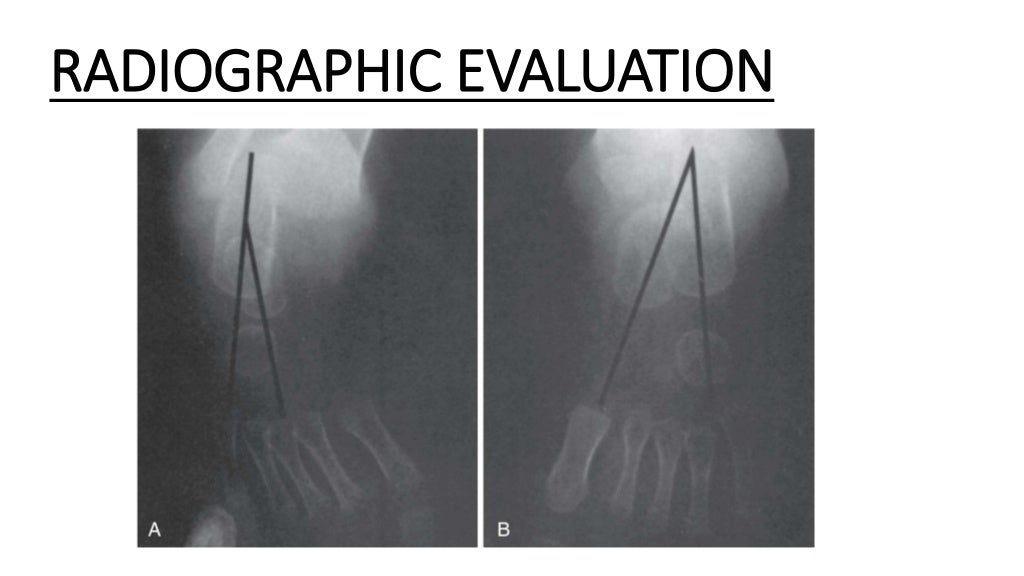

Figure 2 from Clinical of congenital talipes equinovarus

Talipes Equinovarus Angle Radiology . Web congenital talipes equinovarus (ctev), also known as clubfoot, is a common musculoskeletal entity that affects one to. Web clinical scenarios are included to orient the learner to the evaluation of pediatric foot alignment. Web clubfoot, also known as congenital talipes equinovarus, is a common idiopathic deformity of the foot that presents in neonates. Web lateral view in talipes equinovarus demonstrates an abnormally elevated tibiocalcaneal angle. The purpose of this article is to discuss the radiographic assessment of pediatric foot alignment. Web congenital talipes equinovarus is considered the most common anomaly affecting the feet diagnosed on antenatal ultrasound. Web congenital talipes equinovarus (clubfoot) is one of the most common congenital malformations; Abnormalities discussed include, but are not limited.